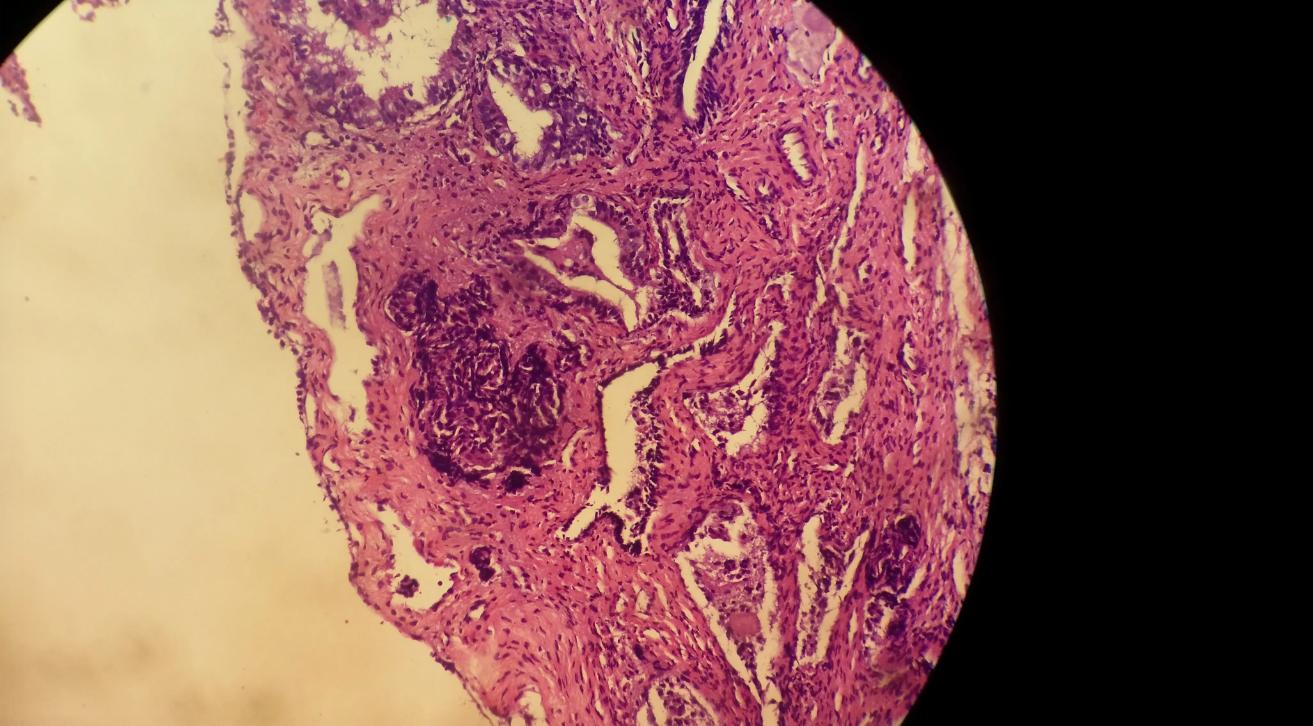

3. Polyp pathology suggests adenomatous or dysplastic changes

Polyps can be classified into benign hyperplastic polyps and adenomatous polyps based on their pathological nature, among whichAdenomatous polyps are precancerous lesionsespecially when accompanied by moderate to severe dysplasia, the probability of malignant transformation is extremely high.

- Intestinal adenomatous polyps including tubular adenoma villous adenoma villous adenoma has the highest malignant transformation rate